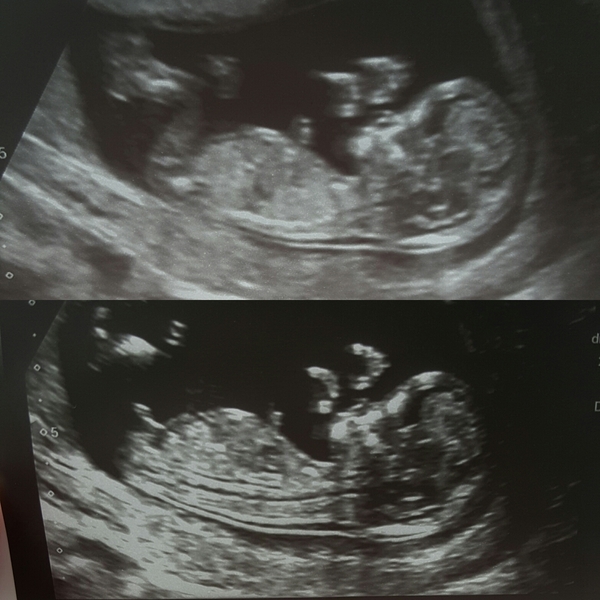

Heya lovely ladies!! Would I be able you join the bus late? Had my 12 week scan on Friday and they have put me 6 days ahead so now I am due September 30th!! Hope everyone is having lovely boring pregnancies Wink with no problems whatsoever!

Here is my scan pic! This will be my second child I have a nearly 3 year old daughter!

Welcome @Birdie963 what a lovely clear scan!